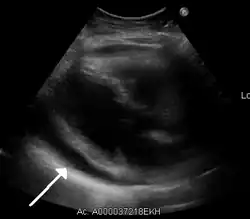

A large anechoic (black) pericardial effusion as seen on ultrasound. Closed arrow: the heart, open arrow: the effusion -

Echocardiogram (ultrasound): when pericardial effusion is suspected, echocardiography usually confirms the diagnosis and allows assessment of the size, location and signs of hemodynamic instability.[4] A transthoracic echocardiogram (TTE) is usually sufficient to evaluate pericardial effusion and it may also help distinguish pericardial effusion from pleural effusion and MI. Most pericardial effusions appear as an anechoic area (black or without an echo) between the visceral and the parietal membrane.[1] Complex or malignant effusions are more heterogeneous in appearance, meaning they may have variations in echo on ultrasound.[5] TTE can also differentiate pericardial effusion based on the size. Although it's difficult to define size classifications because they vary with institutions, most commonly they are as follows: small <10, moderate 10–20, large >20.[5] An echocardiogram is urgently needed for evaluation when there is concern for hemodynamic compromise, a rapidly developing effusion or history of recent cardiac surgery/procedures.[1]